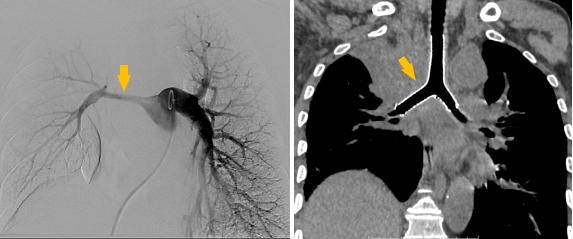

术前受压变窄的右肺动脉和中央气道

介入手术室里,一场无声的战役打响。麻醉科主任闫华凭借高超技术,成功为患者通气建立安全通路,为手术的实施奠定基石。介入科主任贺光辉带领团队细致操作,将一枚Y形气管支架在X线引导下输送至预定位置后精准释放,原本被肿瘤挤压得只剩一丝缝隙的气道被稳稳地撑开。紧接着一枚肺动脉覆膜支架置入到受压变窄的右肺动脉主干内并准确释放,再次造影,使得右肺动脉血流迅速得到改善。